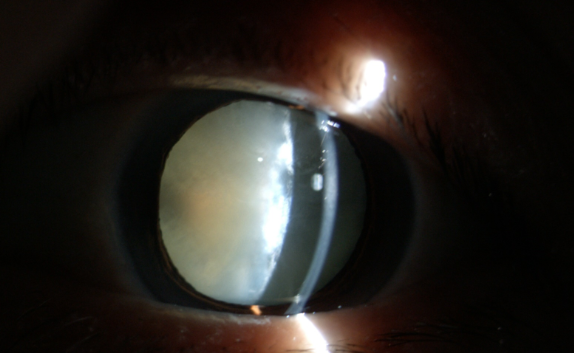

白內(nèi)障癥狀

糖尿病患者合并白內(nèi)障盡早手術(shù)的原因:白內(nèi)障發(fā)生后,不但使患者視力產(chǎn)生障礙甚至失明,還直接影響到醫(yī)生對(duì)眼底的檢查和治療,因?yàn)闇啙岬木铙w阻斷了進(jìn)出光線。因此,糖友們的白內(nèi)障手術(shù)治療,既能解除視力障礙,還能掃除糖尿病視網(wǎng)膜病變的檢查、治療障礙,所以應(yīng)盡早手術(shù)。